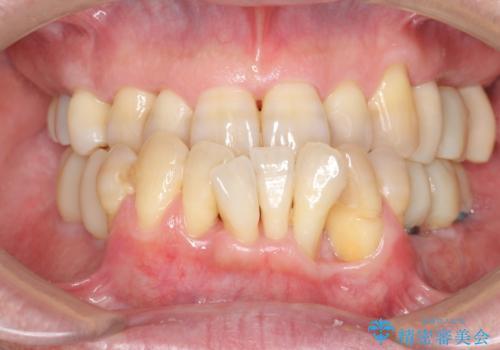

インプラント治療を併用した全顎歯周病治療

- 「仕事のリタイヤに目処がつき、今後は自分の健康にお金をかけたい。しっかりと食事ができる口腔内環境にしてほしい。」と全体的な治療を希望され来院されました。

全体的に重度の歯周病が認められ、抜歯が必要な部位はインプラント治療を、残すことのできる歯には再生治療を含めた歯周病治療を行い全体的な治療を進めてきます。